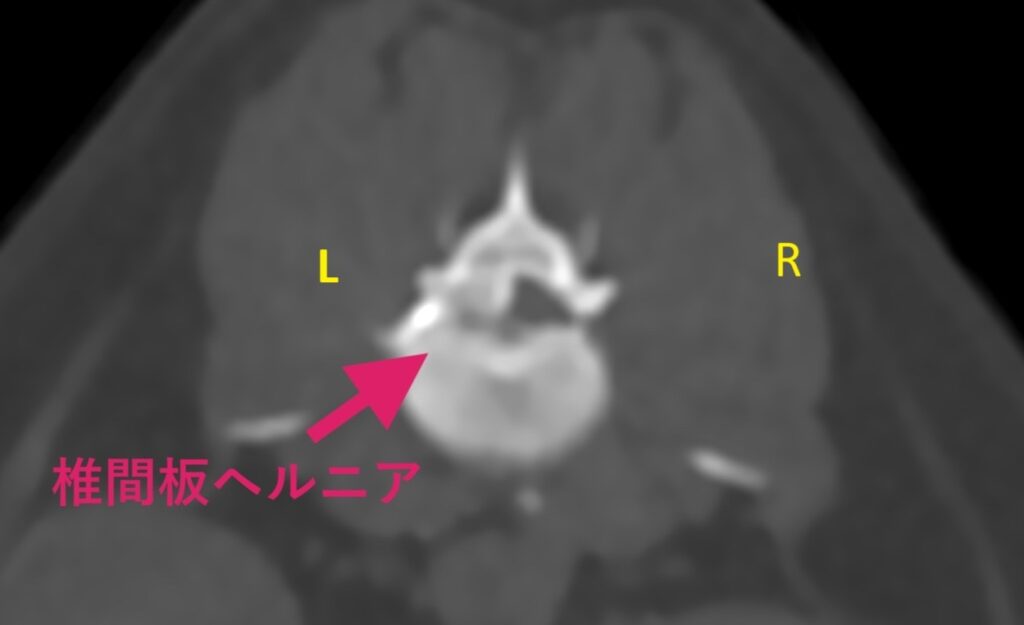

しかしながら第5病日に左後肢の神経症状の悪化が認められた(随意運動が消失)ため、全身麻酔下でCT検査+脊髄造影検査を行いました。

CT検査の結果で、L2-L3の左側から椎間板物質による中等度~重度の脊髄圧迫が認められました。

腰部椎間板ヘルニア(ハンセンI型)